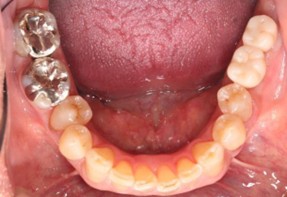

20代 男性

治療後

治療後- リスク・副作用

(薬・注射・レントゲン・CT・データ分析・骨造成・サージカルステント・血液検査・仮歯) - 年齢/性別

- 20代/男性

- 患者の具体的な症状

- 1年前に左上12 右上1の根の治療をし、その後放置していたら、左上2が破折した。

左上2インプラント補綴 左上1右上1オールセラミック装着。

歯根破折と虫歯による痛み、審美障害を主訴として来院。 - 検査方法

- コーンビームCT、レントゲン撮影

- 診断結果

- 左上2 歯根破折

- 治療詳細

- 左上抜歯後、インプラント埋入1本

骨造成あり 局所麻酔

インプラント治療後、左上1右上1セラミック修復2本 - 通院回数

- 9回

- 治療期間

- 12か月